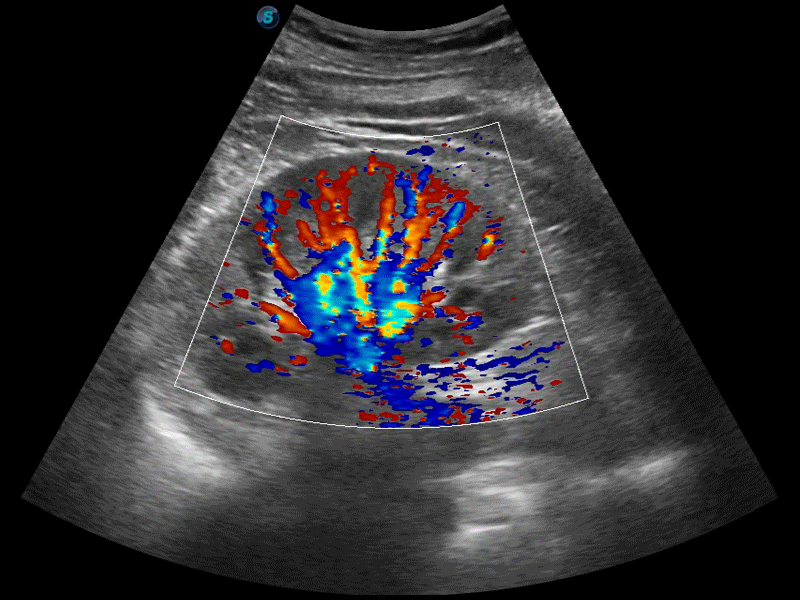

高分辨率血流成像技术提高了对低速血流信号的检测能力。在提高空间分辨率的同时,也克服了血流外溢现象,为用户提供更加真实的血流动力学信息。

通过色彩血流和实时宽景相结合,可观察到完整的静脉或动脉的血流,方便医生检查。实时扫查过程中,如有任何操作失误也可以很容易地进行回扫擦除,而不会中断扫查。